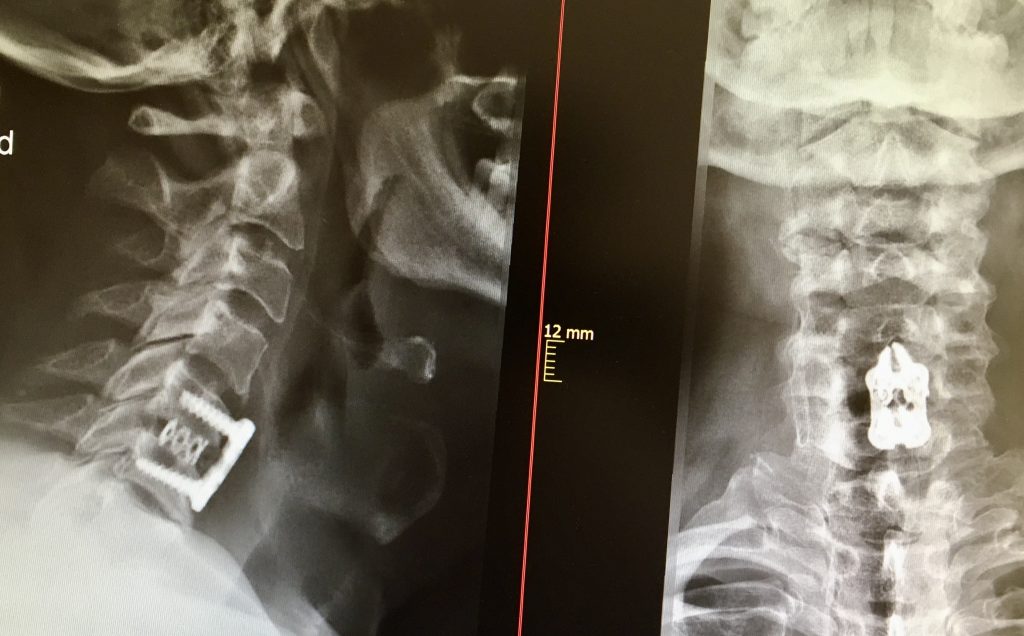

En pacientes jóvenes con discos lesionados sin artrosis asociada, la sustitución del disco por una prótesis cervical nos permite conservar la movilidad del segmento. La cirugía se realiza con una pequeña incisión en la cara anterior del cuello.

El tratamiento de elección en casos donde la hernia se asocia a degeneración discal, sigue siendo en la mayoría de los pacientes la fusión cervical.

En caso de realizar una fusión, se colocan como implantes una caja de soporte entre las vértebras, rellena de injerto óseo propio y se fijan las vértebras utilizando una placa atornillada. Así logramos el doble objetivo de descomprimir la raíz nerviosa y mantener la estabilidad vertebral.

Cuando la indicación por el contrario es la de realizar una artroplastia discal, el implante que se utiliza es una prótesis de disco anclada a las vértebras.